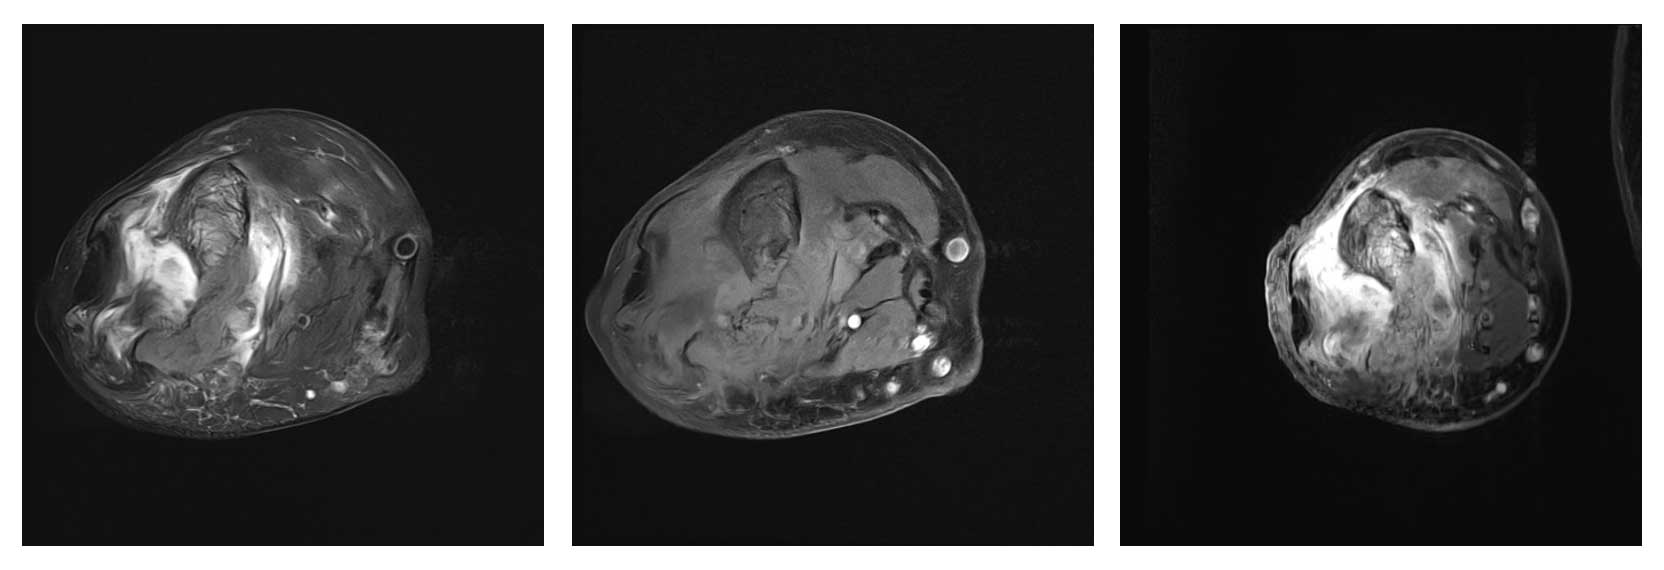

Ameliyat Öncesi: MR’da aynı bölgede ciddi harabiyet ve çevreleyen yaygın ödem görülmekte.